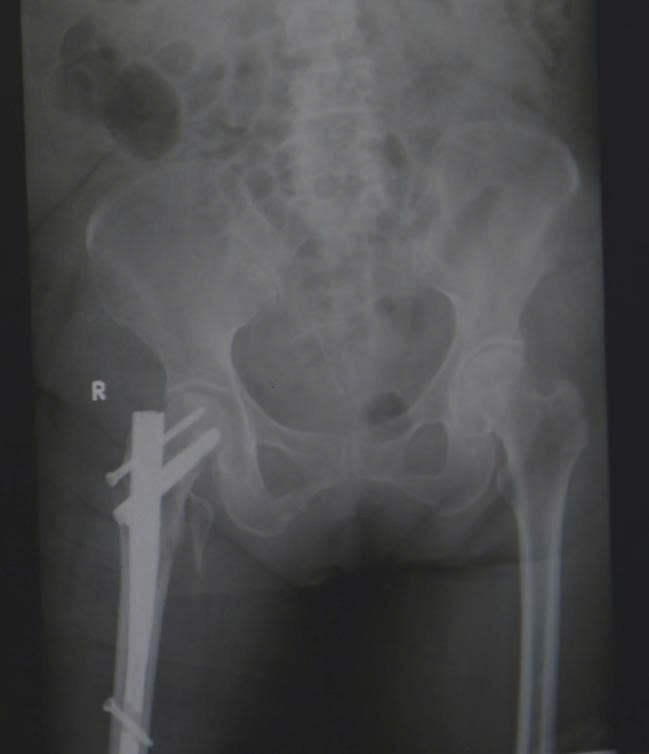

gay-co-xuong-dui.jpg

Hình ảnh phim X-quang sau phẫu thuật đóng đinh nối tụy cho bệnh nhân gãy liên mấu chuyển xương đùi - Ảnh BVCC

Sau khi đánh giá các nguy cơ và đạt được sự ổn định toàn thân, các bác sĩ khoa Chỉnh hình Vi phẫu tiến hành thực hiện ca phẫu thuật đóng đinh nội tủy đầu trên xương đùi – một kỹ thuật phổ biến trong điều trị gãy liên mấu chuyển. Phương pháp này giúp giữ vững cấu trúc xương, cho phép bệnh nhân xoay trở vận động, có thể ngồi dậy và tập vận động sớm.

Sau hai tuần phẫu thuật, bà T. có thể ngồi dậy, xoay trở cử động chân, cụ bà đã có thể ăn uống trở lại. Dù còn yếu, nhưng ánh mắt bà đã ánh lên niềm vui và sự nhẹ nhõm rất nhiều so với thời điểm nhập viện.